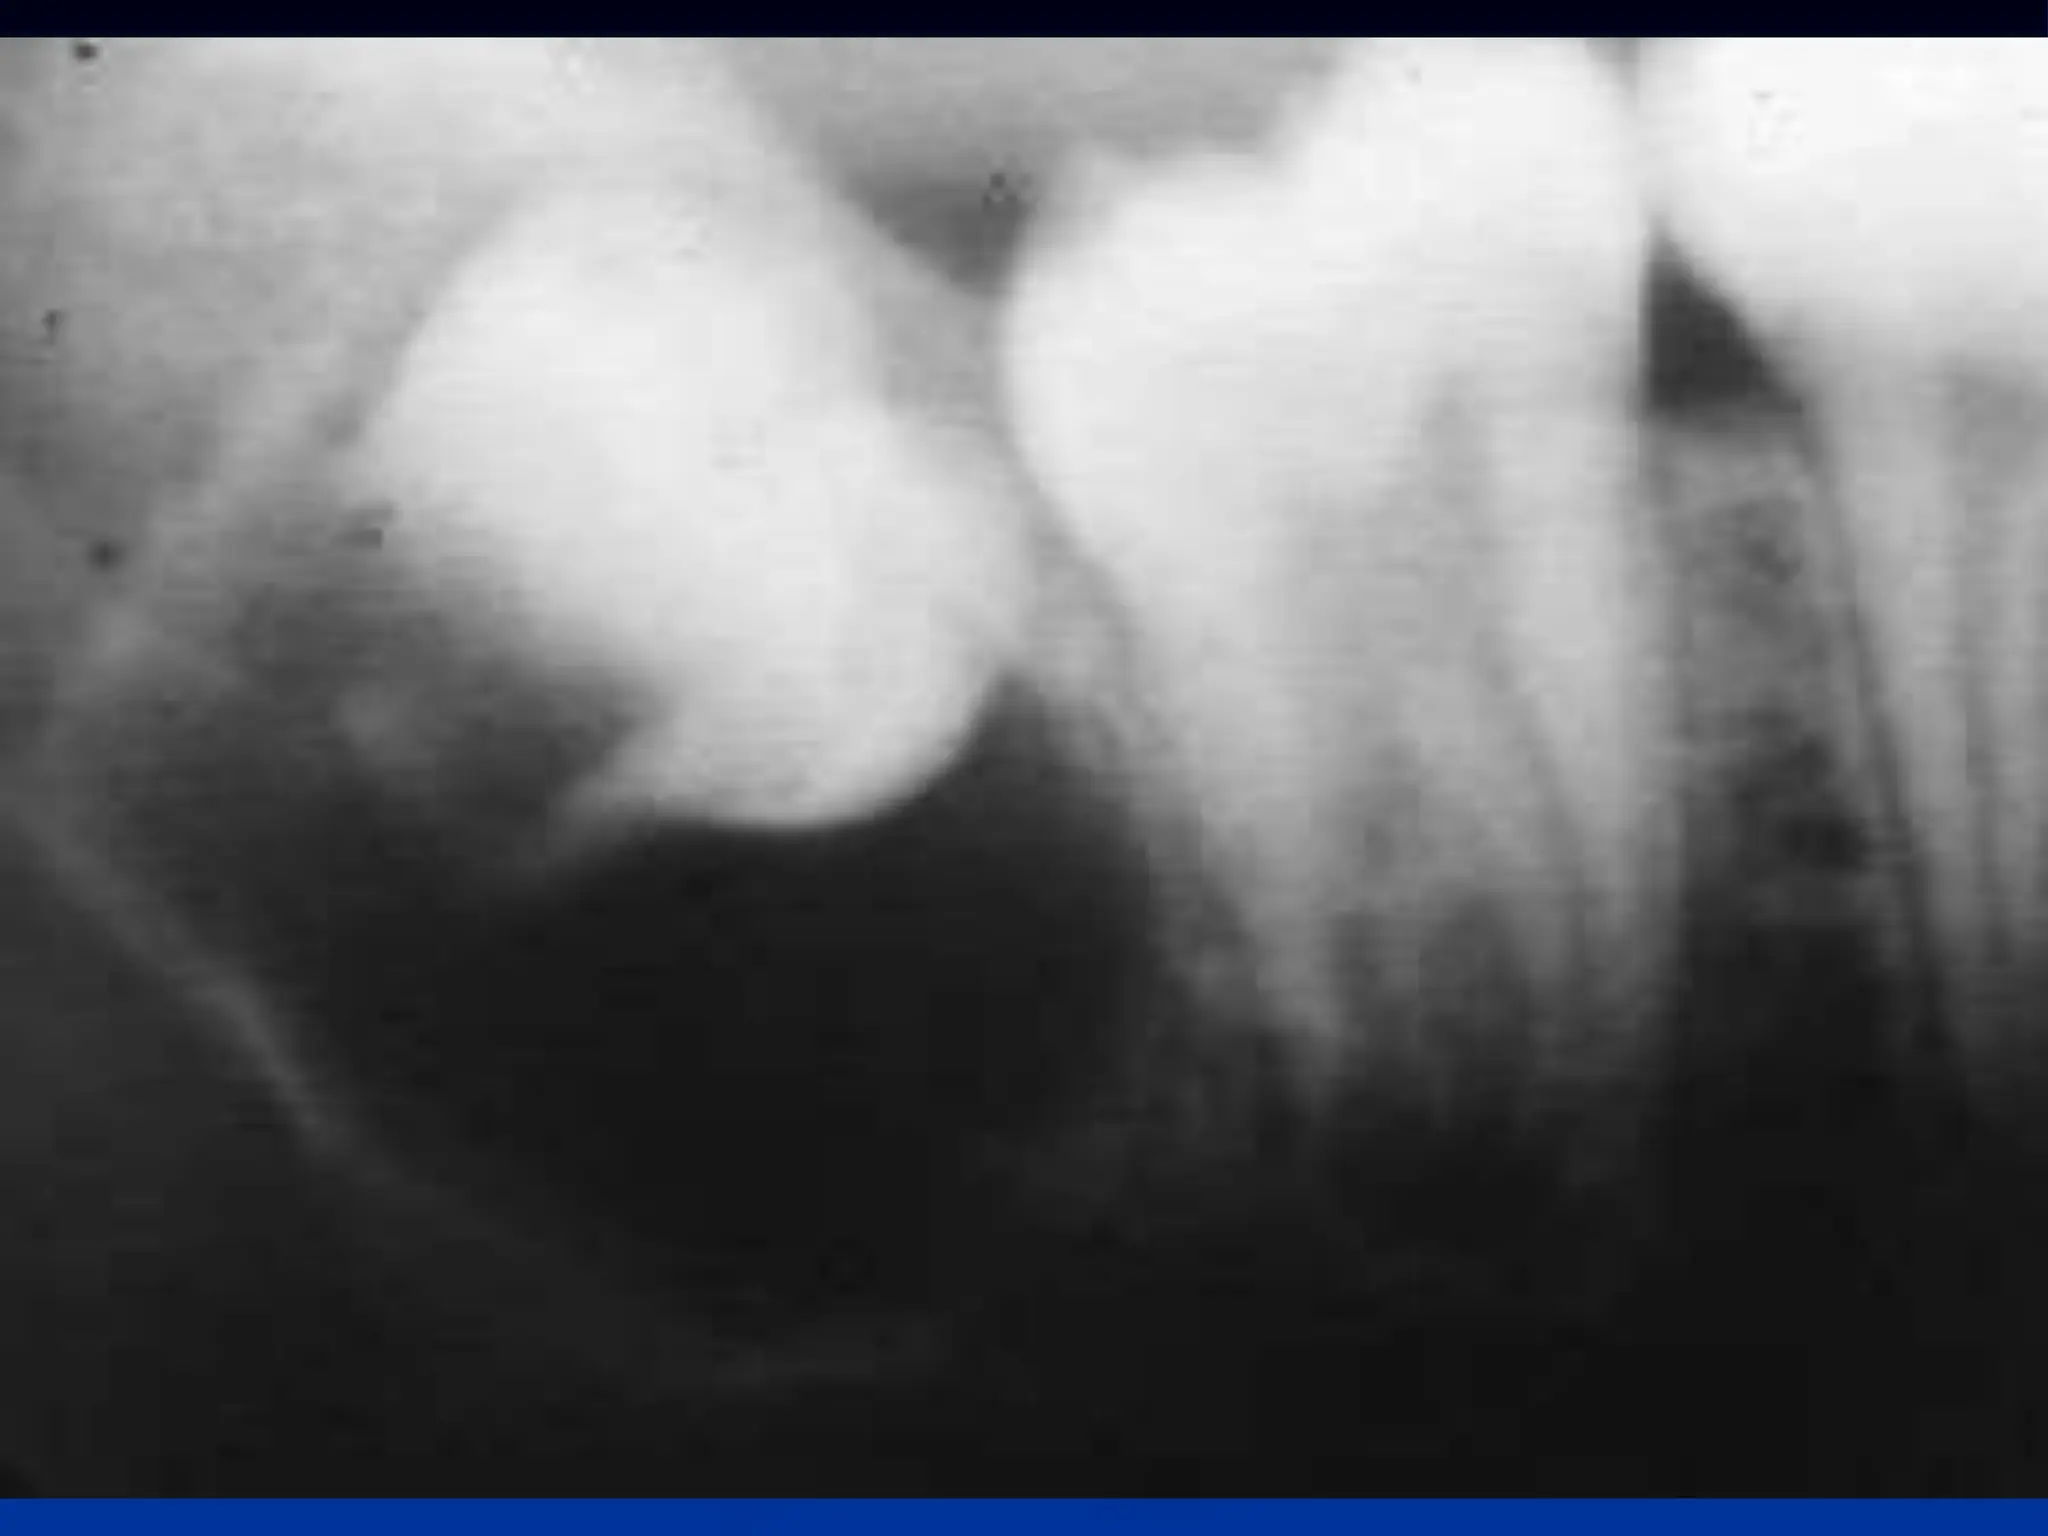

Cementoblastoma

Cementoblastoma - Wikipedia Apical Radiopacities - Radiodontics Cementoblastoma: Features, Diagnosis, and Treatment Cementoblastoma. Classic appearance of a sclerotic tumor fused ... ❇ Benign Cementoblastoma Radiology: ▶ Location: → 78% in ... Cementoblastoma